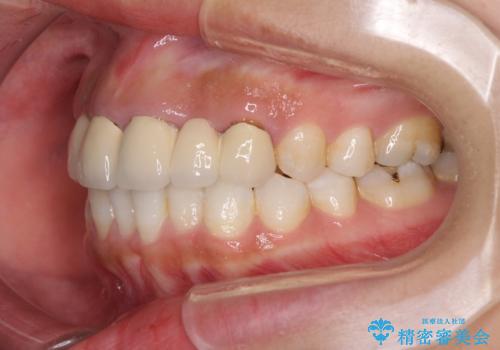

- 審美的ではない上の前歯とデコボコの下の前歯、歯茎が腫れている奥歯を気にして来院された患者様です。

根管治療の必要な歯がいくつかあるため、まずは根管治療を行い、その後インビザラインにて矯正治療を行うこととしました。

矯正治療後に前歯をセラミックブリッジに、奥の銀歯はセラミックインレーやPGAインレー(ゴールドインレー)にて補綴・修復治療を行うこととしました。